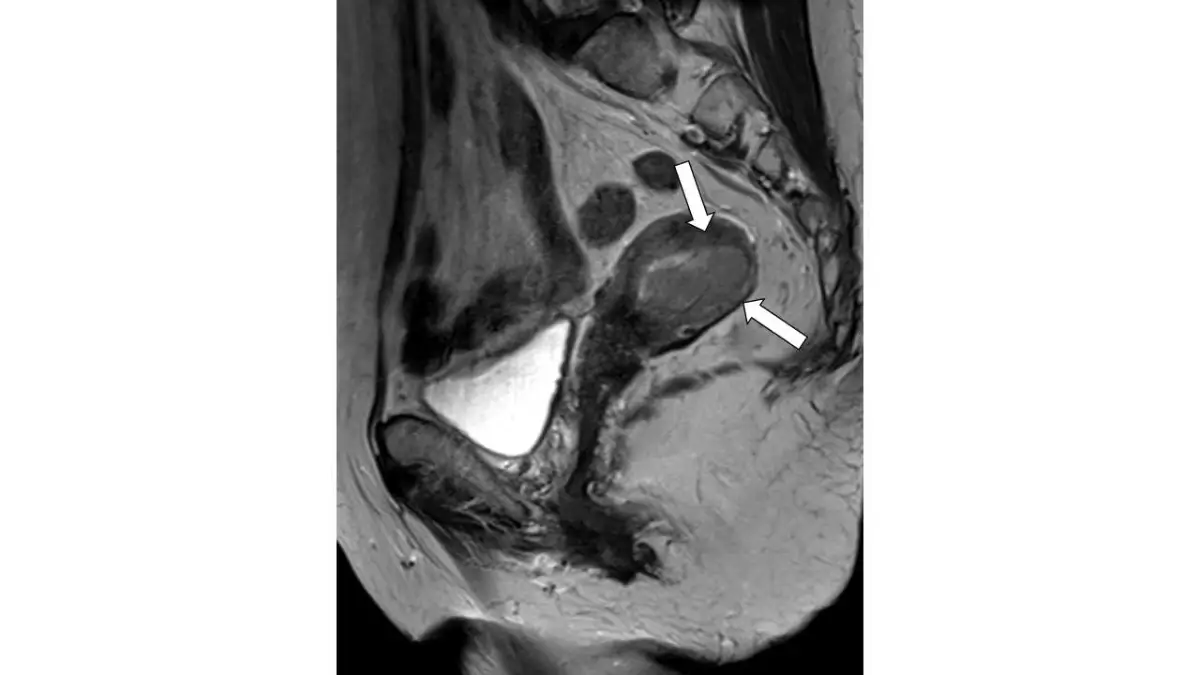

80 歲女性,下腹部磁振造影檢查( T2WI )呈現如圖,箭號所指之敘述何者最正確? 圖片描述

從這張矢狀面T2加權影像可見:

• 前方高亮區域為膀胱內尿液(典型T2高信號);

• 後方低信號帶為直腸及骶尾椎骨骼組織;

• 箭頭指向一橢圓形、位於膀胱後方且緊貼於子宮體部內腔的腫塊,其訊號為中等至稍高於子宮肌層的異質性。

• 腫塊中心未呈現典型液性囊腫完全高信號特徵,顯示為固態或實質性病變;

• 子宮頸部位於更下方,與箭頭區域明顯分離。

根據MRI T2WI顯示,子宮內膜惟正常時呈現略高於肌層之信號;肌層則為低信號,兩者間的交界(junctional zone)被箭頭所示病灶所破壞,暗示內膜來源的實質性腫瘤侵襲了肌層。 (insightsimaging.springeropen.com)